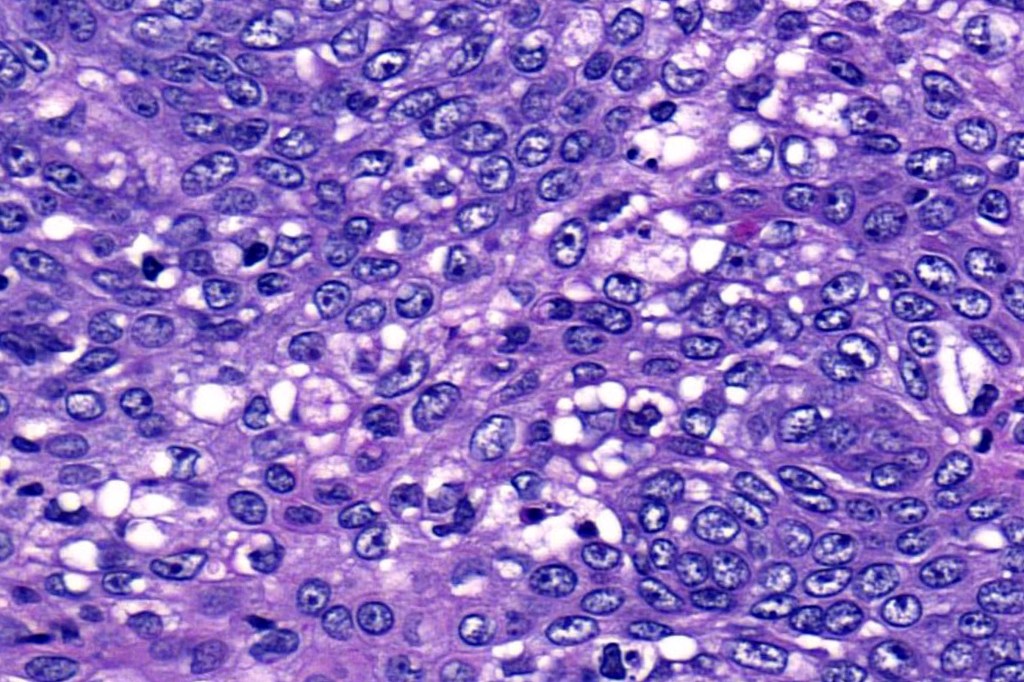

•Tumors are composed of an admixture of darkly staining basaloid cells with hyperchromatic or vesicular nuclei and more obvious sebaceous cells with eosinophilic, bubbly, multivacuolated cytoplasm frequently indenting the nucleus (scalloped)

•Often mitoses are numerous and abnormal forms evident

Sebaceous carcinoma from a patient with Muir-Torre syndrome kindly shared by Dr. Antonina Kalmykova.